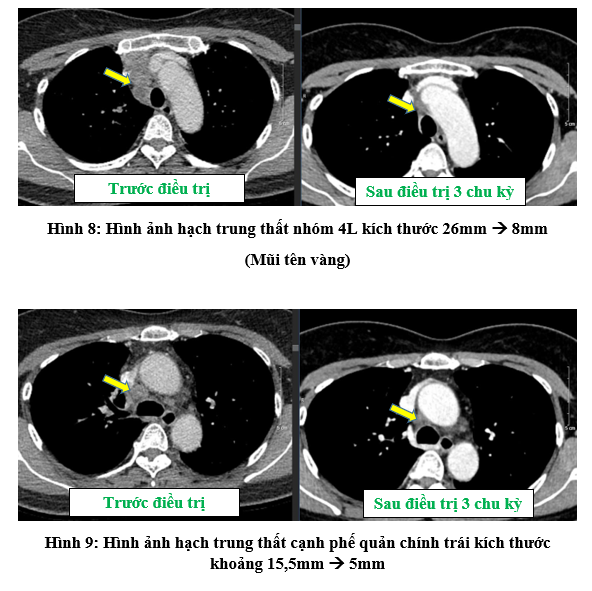

- Chụt cắt lớp vi tính lồng ngực:

- Chất chỉ điểm khối u sau 3 chu kỳ điều trị đã giảm và trở về bình thường: CEA: 1,29 ng/ml (bình thường: < 4,3 ng/ml);  Cyfra 21-1: 2,28 ng/ml (bình thường: < 2,37 ng/ml).